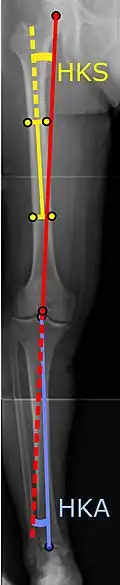

Ángulos comúnmente medidos antes de la cirugía de reemplazo de rodilla: |

Para indicar el reemplazo de rodilla en caso de osteoartritis, su clasificación radiográfica y la gravedad de los síntomas deben ser sustanciales. Dicha radiografía debe consistir en radiografías en carga de ambas rodillas: AP, lateral y 30 grados de flexión. Es posible que las proyecciones AP y lateral no muestren un estrechamiento del espacio articular, pero la vista en flexión de 30 grados es más sensible al estrechamiento. También se utilizan proyecciones de longitud completa para ajustar la prótesis para proporcionar un ángulo neutro para la extremidad inferior distal. Dos ángulos utilizados para este propósito son:

- Ángulo cadera-rodilla-eje (CRE),[8] un ángulo formado entre una línea que pasa por el eje longitudinal de la diáfisis femoral y su eje mecánico, que es una línea desde el centro de la cabeza femoral hasta la muesca intercondilar de la diáfisis femoral. fémur.[10]

- Ángulo cadera-rodilla-tobillo (CRT),[9] que es un ángulo entre el eje mecánico femoral y el centro de la articulación del tobillo.[10] Normalmente se encuentra entre 1.0° y 1.5° de varo en adultos.[11]